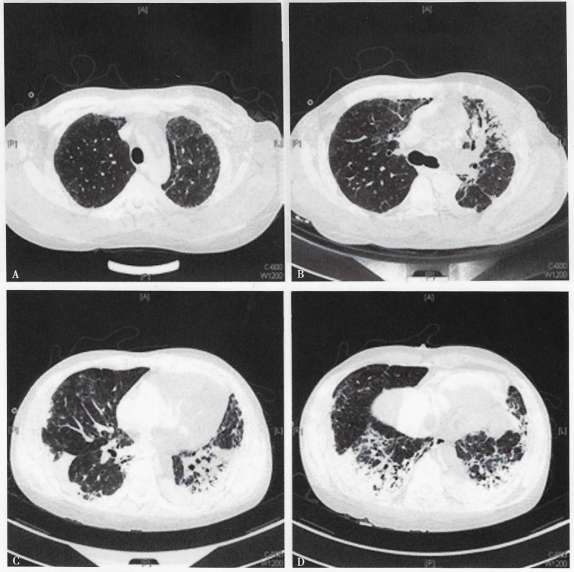

2016年12月中旬患者无诱因出现咳嗽,初为白痰,后为黄痰,量少,伴左侧季肋部疼痛和胸闷不适,未作特殊处理。12月27日患者可疑受凉后出现发热伴神志淡漠,体温最高39.1℃,来我院急诊,查尿隐血阴性,肌酐128 μmol/L,白细胞计数15×109/L;胸部CT(2016年12月28日)提示两肺磨玻璃影伴多发斑片密度增高影,左侧明显(图1)患者要求去外地就诊,拒绝住院。12月30日夜间再次高热,伴意识不清,再次来我院急诊查血常规:CRP 319 mg/L,白细胞11.8×109/L,体温39.5℃,予气管插管呼吸机辅助呼吸,收入RICU。

图1 患者胸部CT

入院后考虑患者有可疑受凉诱因,长期使用激素,WBC及CRP升高,两肺片状影,予比阿培南、莫西沙星及伏立康唑抗感染治疗,考虑重症肺炎。胸部CT可见局部胸膜下线及牵拉性支气管扩张(图1),感染继发或合并两肺弥漫性病变可能,予甲泼尼龙120 mg,bid,静脉滴注,并完善自身抗体、细胞免疫等检验。

经上述治疗3 d后患者体温峰值波动在38℃以下,神志转清,复查动脉血气分析,氧合较前明显改善,自主呼吸试验通过气道保护能力尚可。2017年1月6日拔除气管插管并复查胸部CT及头颅CT。胸部CT提示两肺病变较2016年12月28日进展,左肺体积较前变小,纵隔左偏,右下肺实变较前加重(图2),头颅CT未见明显异常。

图2  胸部CT提示两肺病变较前进展